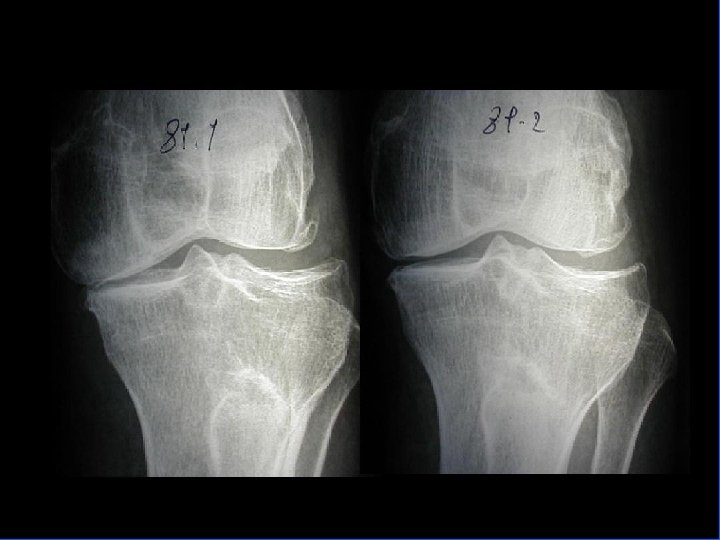

Arthrose fémoro-tibiale Clinique • Examen : debout / couché • Debout s’intéresse aux déviations axiales – genu-varum ou genu-valgum voire genu-recurvatum • Décubitus dorsal pour différentes mobilités – Craquement audible ou palpable à la flexion cartilage) (atteinte – Recherche épanchement (choc rotulien) – Déformations (arthrose évoluée: aspect globuleux voir flessum) – Teste stabilité antéro-post (conservées) et latérales

Arthrose fémoro-tibiale Iconographie • Radiographie : – Face en appui bipodal – Profil – Schuss (face en charge à 30° de flexion) pour compartiment post • Signes: – Pincement interligne – Ostéophytose – Ostéosclérose sous-chondrale avec géodes